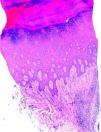

HistopatologíaEl estudio histopatológico reveló una hiperqueratosis ortoqueratósica con hiperplasia epidérmica subyacente. En la dermis existía un infiltrado inflamatorio mixto de predominio linfoplasmocitario, proliferación vascular y signos de sangrado crónico (fig. 2). Con técnicas histoquímicas convencionales para la detección de microorganismos se identificaron cúmulos de bacterias gram positivas, conformando estructuras de centro granular basófilo y collarete eosinófilo periférico (fenómeno de Splendore-Hoeppli) (fig. 3).